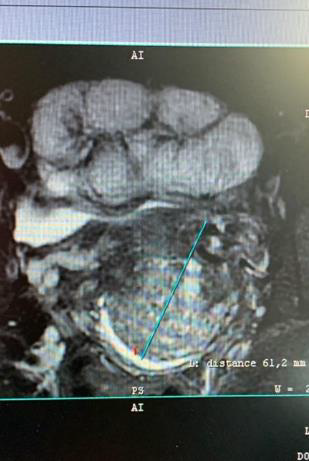

A 44 old Caucasian woman came to our attention from another Institution in May 2020 for AUB. The patient is gravida 1, para 1, BMI 23 kg/m2, with an absence of risk factors for inherited malignancies, in good health, and underwent regular clinical check-ups. No sign of Peutz-Jeghers syndrome was found. Clinical assessment showed the presence of an enlarged and easily bleeding portio with crumbly consistency, despite MRI showed no alteration (Figure 1-2).

Figure 1: The MRI image above was considered normal, although polycystic and solid component enhancement should be alert to MDA.

Figure 2: Sagittal section of the cervix, with multicystic lesion and solid component. No invasive tumour mass was found.